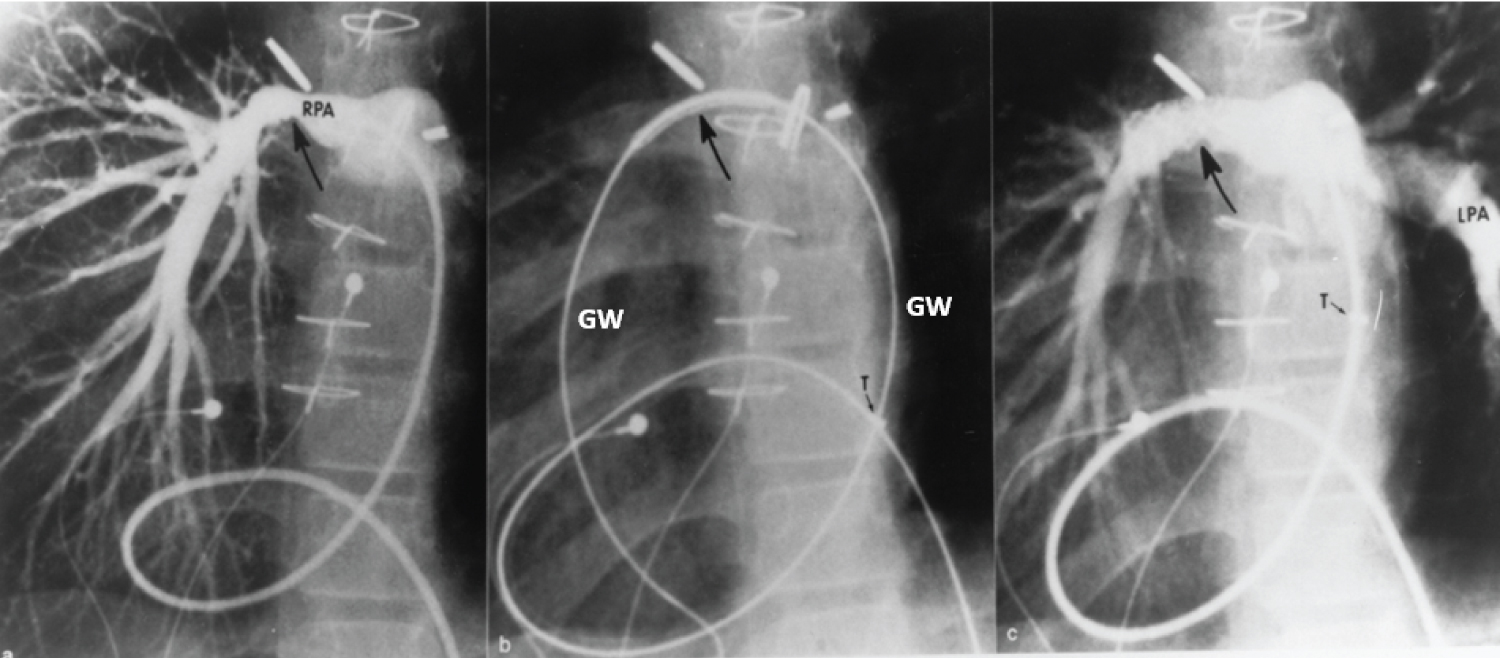

In addition, a number reviews and editorials pertaining to stents, published by the author, were reviewed and these include their usefulness in the treatment of branch pulmonary artery stenosis (Figure 18) [96,100,102,105], coarctation of the aorta (Figures 19) [96,100,102], obstructed right ventricular outflow conduits (Figures 20) [100,102] native right ventricular outflow obstructions in tetralogy of Fallot [100,106], occluded/obstructed surgical shunts [103,105], systemic venous and pulmonary venous stenoses [100,102], and other sites. Future directions with regard to the use of stents in growing children [107,108] were also discussed.

Figure 18: a) Selected cine frame from a 30° right anterior oblique view, demonstrating a narrowed right pulmonary artery (RPA) (arrow); b) The position of the stent before implantation (large arrow), and c) The improved size of the pulmonary artery after stent deployment. Note the tortuous course of the catheter in a patient with dextrocardia and morphologic left ventricle to pulmonary artery conduit (not shown). The position of the tip (T) of the long blue Cook sheath is shown. Because of its length (65 cm), the sheath could not be advanced any further, but the stent catheter could easily be maneuvered across the stenotic right pulmonary artery over the guide wire (GW). LPA: Left Pulmonary Artery [102]. View Figure 18